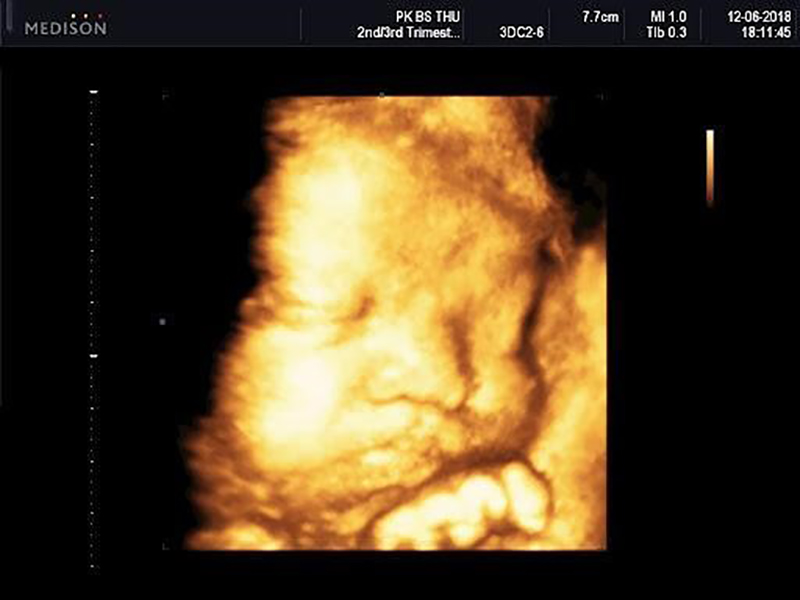

Siêu âm 4D là kỹ thuật siêu âm 4 chiều với một chiều thời gian và 3 chiều không gian, nhờ vậy bác sĩ và mẹ có thể nhìn rõ được cử chỉ, hình hài đáng yêu của bé trong thời gian thực hiện. Thậm chí nếu may mắn, bạn còn có thể chớp được hình ảnh thiên thần nhỏ đang cười, khóc nhè hay cau mày,…

Có thể nói, siêu âm 4D đã đưa vào công nghệ chẩn đoán hình ảnh một bước ngoặt hiện đại mới, cải tiến hơn so với siêu âm 2D và 3D. Khác với kỹ thuật 2D cho ra hình ảnh đen trắng với những con số chưa rõ ràng thì siêu âm 4D sẽ cho hình ảnh màu, sắc nét, chính xác, chân thật và tạo ra những hiệu ứng giống như đang xem video trực tiếp. Qua đó, bác sĩ sẽ dễ dàng phát hiện được những dị tật bẩm sinh ở trẻ như hở hàm ếch, các dị tật về não, hội chứng Down, thai phù,… để có hướng can thiệp sớm.